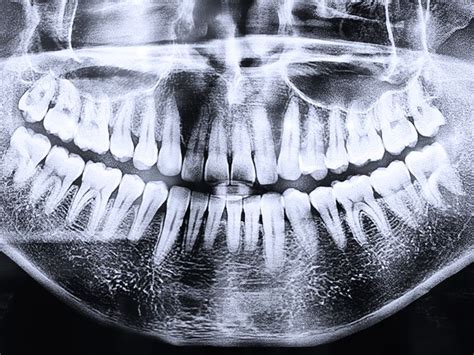

Pruebas de Diagnóstico

Contratar un seguro dental te permite contar con todas las pruebas necesarias para comprobar el estado de tu salud bucodental y llevar a cabo los tratamientos necesarios. Según la póliza que elijas, podrás contar con radiografías o TAC dental. Este tipo de diagnósticos, ayudan a estudiar correctamente el estado de tus dientes y encías para comprobar su estado y saber los procedimientos que es necesario realizar.

¿Sientes molestia al tomar bebidas frías o calientes? Los seguros que cubren tratamientos para la sensibilidad pueden ayudarte. Entre las pruebas cubiertas por un seguro dental están las radiografías intraorales, panorámicas u ortopantomografías, así como la lateral de cráneo.

- Diagnóstico por imágenes, con radiografías, ortopantomografía, telerradiografía y estudio radiológico ATM.